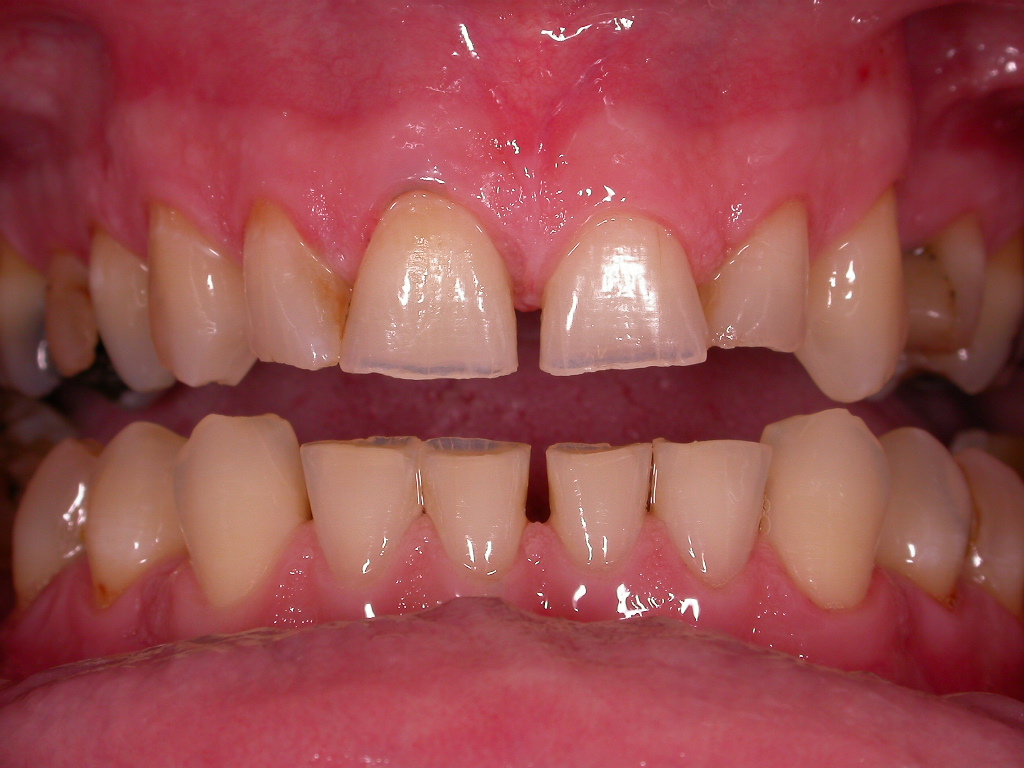

Teilweise Nichtanlage bleibender Zähne mit teilweise noch vorhandenen Milchzähnen, abgesunkener, lückiger Bisslage

Vorher: Teilweise Nichtanlage bleibender Zähne mit teilweise noch vorhandenen Milchzähnen, abgesunkener, lückiger Bisslage

Komplettbehandlung mit Bisshebung, Setzen von Implantaten als Ersatz für die Milchzähne, Schaffen einer völlig neuen, ästhetischen Gesamtsituation mit vollkeramischen Kronen und Brücken

Nachher: Komplettbehandlung mit Bisshebung, Setzen von Implantaten als Ersatz für die Milchzähne, Schaffen einer völlig neuen, ästhetischen Gesamtsituation mit vollkeramischen Kronen und Brücken